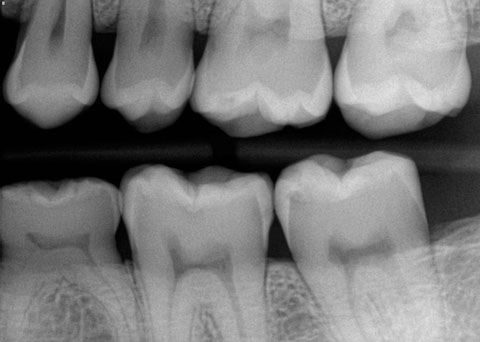

One of the best ways to improve your oral health is to understand its current state and how its changed since your previous appointments. For this reason we have invested in advanced computer systems and digital imaging software so your records don't have to be a secret or difficult to understand.  During your appointment we will discuss diagnostic images from your current and previous appointments, so you understand any minor changes worth monitoring or major problems that require intervention. Your images are presented to you on large 34" monitors that make it easy for you to see how healthy your mouth is, or any damages. We also keep diagrammed digital charts that allow for you to easily see the type and location of previous work you have completed.